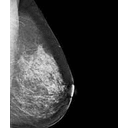

mamografia_Sep_2008[1].jpg